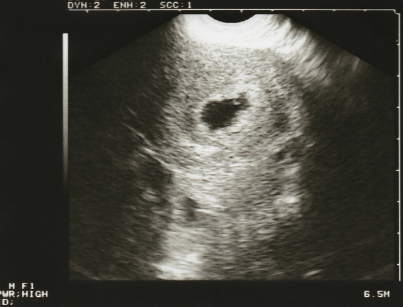

태움이 보이다.

당신은 배아라고 불리는 아기의 모습을 뱃속에서 볼 수 있다. (임신 6주경)